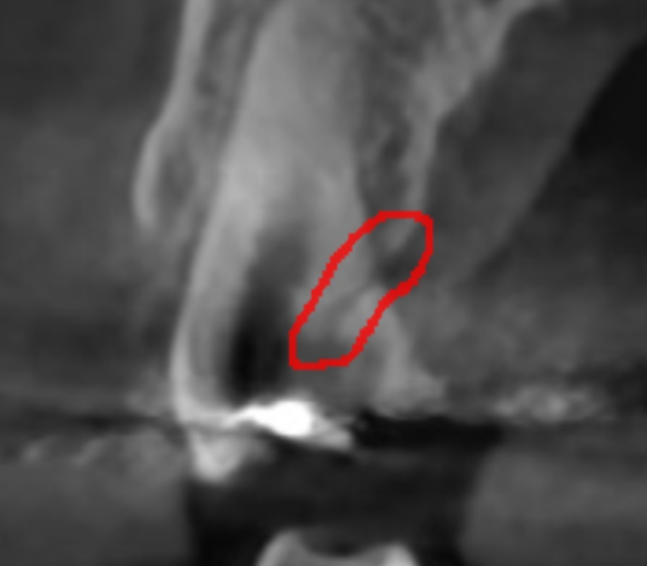

특히 치아 금이 간 경우는 육안으로 확인하기 어려운데

증상에 의존하기보다는

ct 장비 등을 활용해 정확히 확인해보는게 좋습니다.

ct로 금이 간 부분을 발견했어요!

육안으로 보기 힘든 부분까지 정밀하게 확인이 가능하여

원인 부분만 치료할 가능성이 높아집니다.